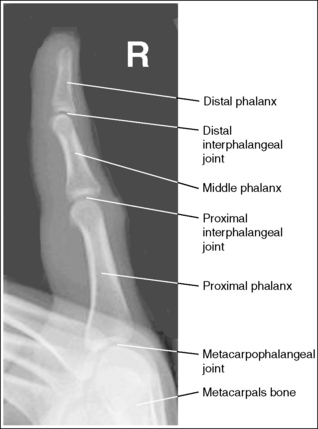

See Figure 4-10 and Box 4-4.

The digit of interest is in a lateral projection. The anterior aspect of the middle and proximal phalanges demonstrates midshaft concavity, and the posterior aspects of the phalanges show slight convexity.

• A lateral finger projection is accomplished by rotating the affected finger 90 degrees from the PA projection (Figure 4-11). Whether the hand is rotated internally or externally to obtain this goal depends on which direction will bring the finger closer to the IR. Typically, when the second and third fingers are imaged, the hand is rotated internally and, when the fourth and fifth fingers are imaged, the hand is rotated externally.

• Distinguishing lateral projection from rotated projection. To understand the difference between a truly lateral digit projection and a lateral projection that is rotated, study a finger skeleton in lateral and PA and AP oblique projections. Note how the midshaft concavity of the middle and proximal phalanges varies as the digit is rotated. In a lateral projection, the anterior aspect of these phalanges is concave, but the posterior aspect demonstrates slight convexity. In PA and AP oblique projections, both sides of the middle and proximal phalangeal midshafts demonstrate concavity, but the side toward which the anterior surface is rotated demonstrates a greater degree of concavity than the side toward which the posterior surface is rotated. The soft tissue width at either side of the phalanx also changes in the lateral and PA and AP oblique projections. More soft tissue is present on the side of the phalanges toward which the anterior surface is rotated (see Image 7).

The IP joints are visible as open spaces, and the phalanges are not foreshortened.

• The IP joints are open, and the phalanges are demonstrated without foreshortening as long as the finger was positioned parallel with the IR and the central ray was perpendicular to and centered with the PIP joint.

• When the third and fourth digits are imaged, they are positioned at a greater OID than the second and fifth digits. To keep the third and fourth digits parallel with the IR, it may be necessary to place an immobilization device beneath their distal phalanges. When a finger is not positioned parallel with the IR and perpendicular to the central ray, the IP joint spaces are closed and the phalanges are foreshortened.

The PIP joint is at the center of the exposure field. The distal, middle, and proximal phalanges and the metacarpal head of the affected digit are included within the collimated field.

• Center a perpendicular central ray to the PIP joint to place it in the center of the image. Open the longitudinal collimation to include the distal phalanx and the metacarpal head. Transversely collimate to within 0.5 inch (1.25 cm) of the finger skin line.